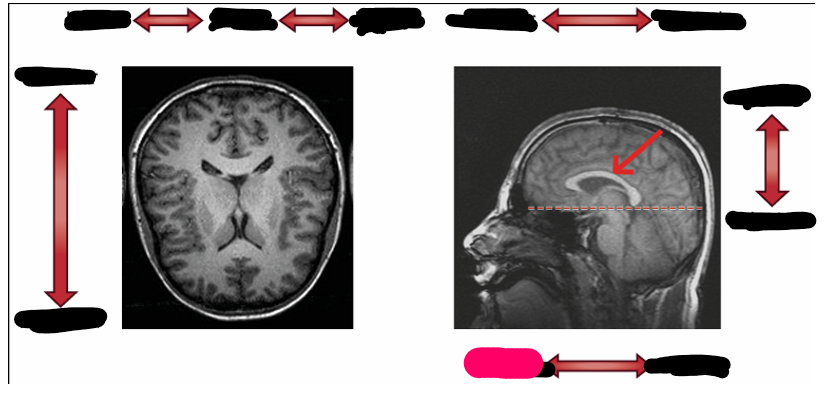

sagittal

horizontal/ transverse

coronal

dorsal

ventral

longitudinal fissure

central fissure

parieto-occipital fissure

corpus callosum